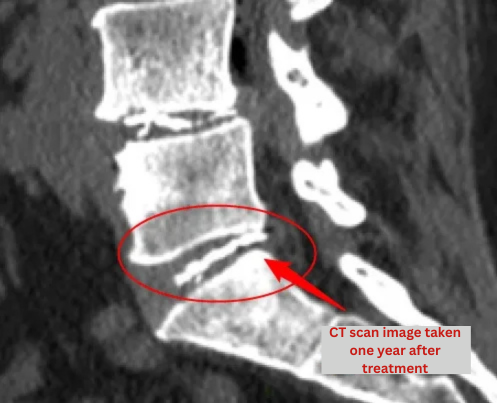

• Post-treatment imaging (CT or X-ray) is used to confirm that disc repair has been achieved.